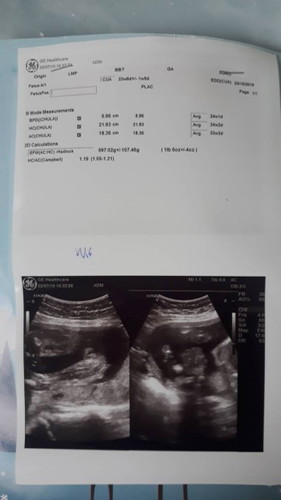

ลูกสาวปีนี้ คุณเเม่ตั้งชื่ว่าอะไรกันบ้างค้ะ อยากรู้จัง ตอนนี้ 24 w เเล้ว ได้ลูกสาว หาชื่อให้ลูกอยู่เรยค้ะ